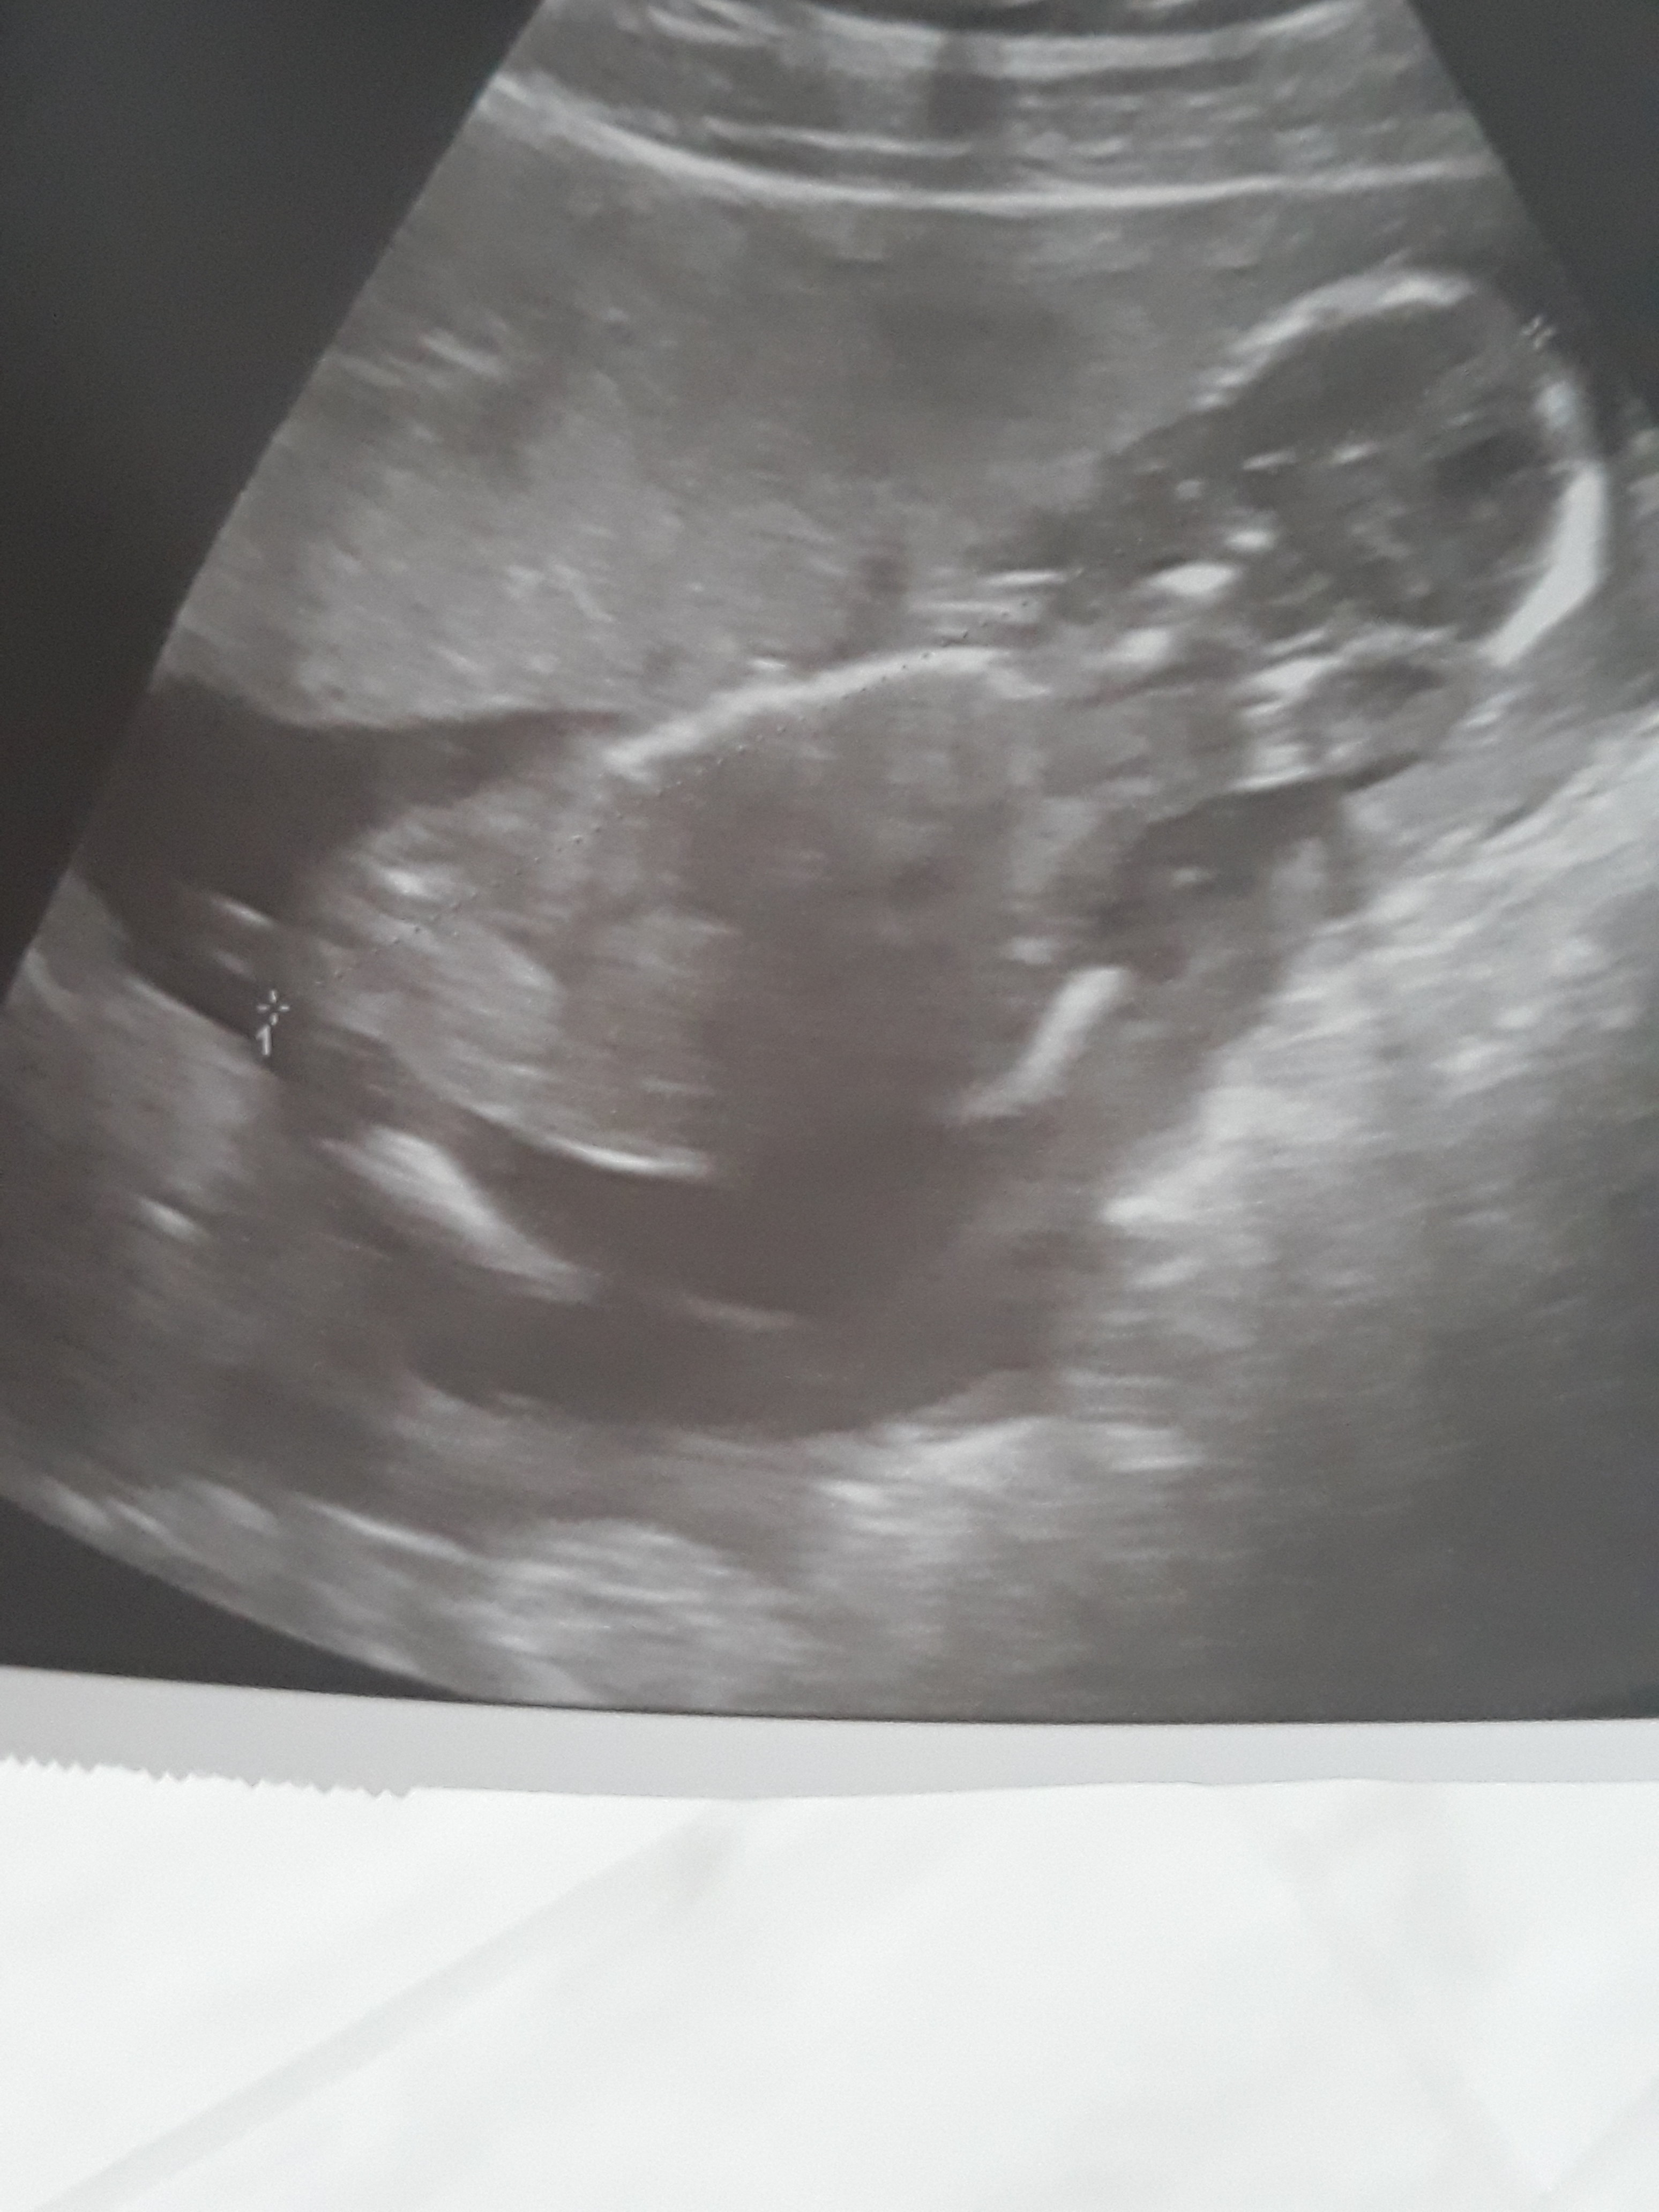

Czerwcowe Mamy 2019

Niestety zdjecia usg nie mam ale widzialam tego malucha jak tam skakal albo inaczej - skakala i kopala [emoji13][emoji7][emoji7] on tez nie mial jakos wątpliwości co do plci [emoji7][emoji13][emoji13]